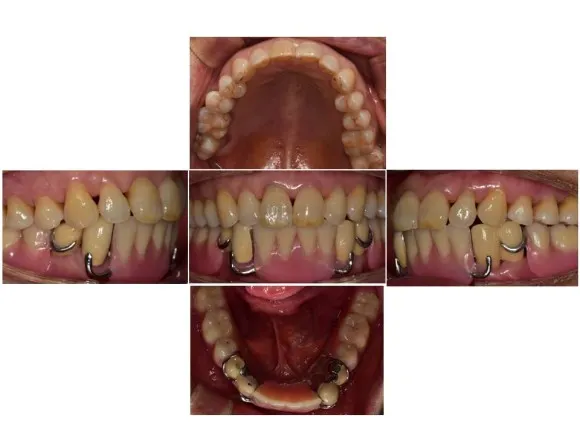

전후 사진으로 비교해보겠습니다.

부분틀니 장착 전

부분틀니 장착 후

최종으로 마무리된 후 사진입니다.

웃을 때 보이던 고리가 사라져 웃었을 때 깨끗한 모습으로 수정되었습니다.